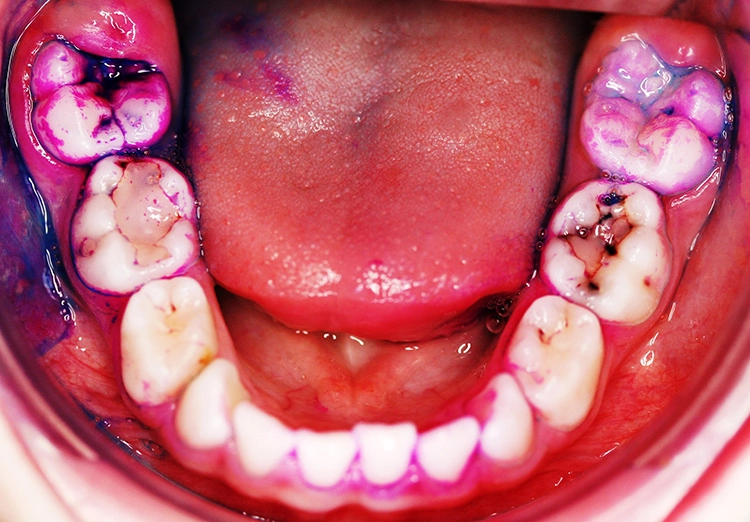

Erst eine weitergehende röntgenologische Untersuchung zeigt das ganze Ausmaß des Kariesbefalls (Abb. 1c). Das Kind wies an fast allen Milchzähnen bereits Dentinkaries, zum Teil auch schon sehr tiefe Läsionen (Zahn 75), auf. Solch ein Befund scheint bei zahlreichen konventionell-restaurativen Maßnahmen bei altersentsprechender mäßiger Kooperation (fast) nur in Narkose behandelbar.

Beim Kleinkind spielt primär die frühkindliche Karies eine Rolle, die initial meist durch kariöse Läsionen an den Oberkieferfrontzähnen gekennzeichnet ist (Abb. 2). Im permanenten Gebiss unterliegen die Kauflächen der durchbrechenden 1. und 2. Molaren insbesondere in der ca. 1,5 Jahre dauernden Durchbruchsphase einem erhöhten Kariesrisiko. Während kieferorthopädischer Maßnahmen mit festsitzenden Apparaturen bei Jugendlichen sollte besonderes Augenmerk auf die Beurteilung der Mundhygiene, wie dem Vorhandensein kariogener Plaque auf Kariesrisikoflächen (Abb. 3), und Kariesaktivität gelegt werden, um frühzeitig präventiv einzugreifen und klinische Bilder mit kariösen Läsionen an fast allen Zähnen möglichst zu vermeiden (Abb. 4).